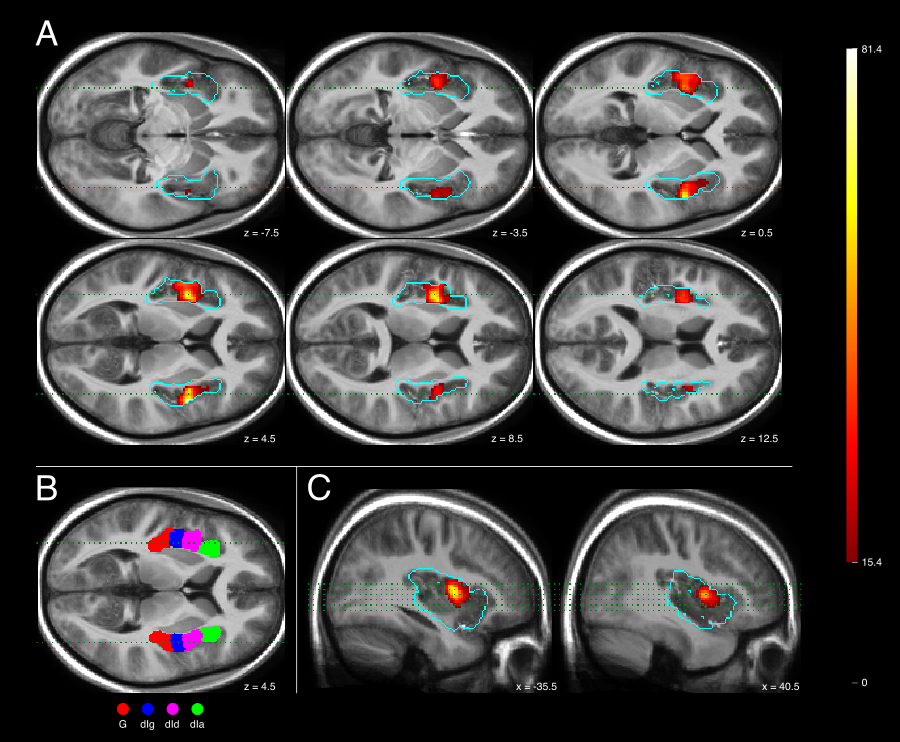

Voxel-wise analyses reveal increased activity in the bilateral dorsal mid-insula during interoceptive attention (attending to one’s heartbeat) compared to exteroceptive attention (attending to auditory white noise). Layer-specific analyses further demonstrate that this difference in activity is significantly higher in upper compared to lower cortical layers. This activation pattern persists after accounting for potential vascular artifacts through a deconvolution analysis with a physiological point spread function (PSF).

Figure 2: Classical Analysis of Interoceptive Attention Effects on Insula Activity.